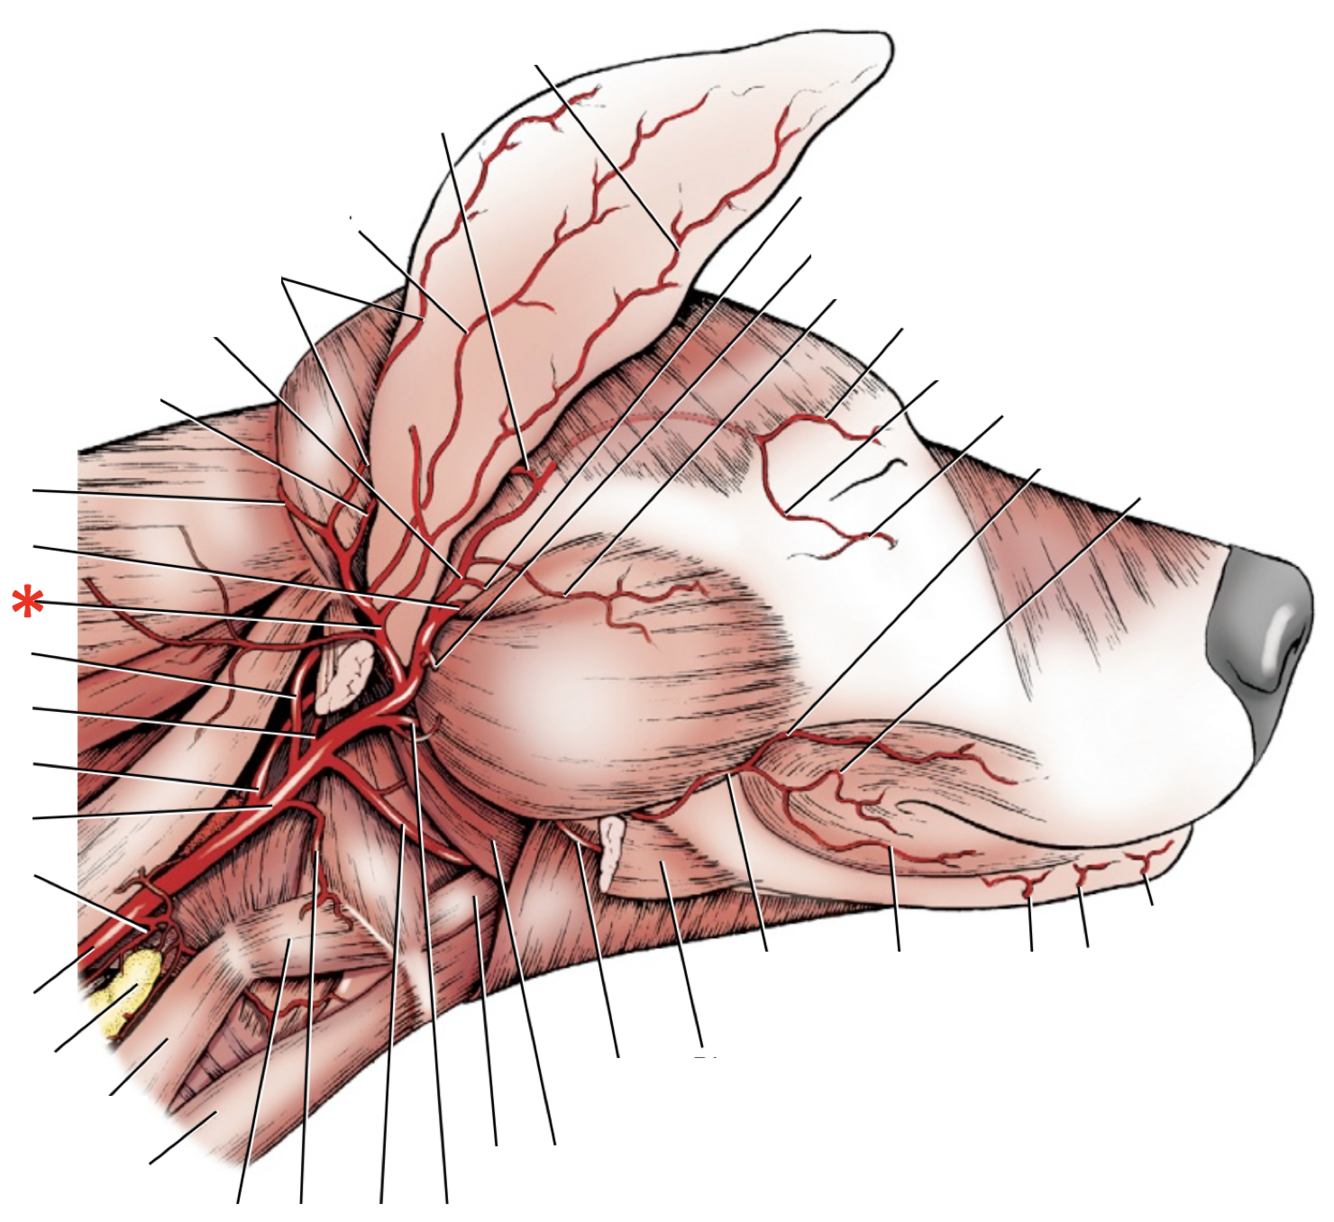

Name the nerves of the Vagus group (with CN-numbers)

* *N.* *glossopharyngeus* (CN-IX)

* *N. vagus* (CN-X)

* *N. accessorius* (CN-XI)

26

**N. glossopharyngeus (CN-IX)**

27

**N.** **accessorius (CN-XI)**

28

**N. vagus (CN-X)**

29

**Ganglion** **distale** **of n. vagus**

30

List the branches and ganglia of n. vagus

* *Ggl.* *proximale*

----------*For.* *Jugulare*----------

* *R.* *communicans* *cum n. glossopharyngeo*

* *Rr.* *pharyngea*

* *R. oesophagus*

* *Ggl. distale*

* *Tr. vasosympaticus*

* *N. depressor*

* *N. laryngeus cranialis*

* *R. externus*

* R. internus

31

**Tr. vasosympaticus**

32

**N.** **accessorius (CN-XI)**

33

**N.** **glossopharyngeus** **(CN-IX)**

34

*Tr.* *vagosympatheticus* is formed by...

* *N. vagus*

* *Tr. sympathicus*

35

*Tr.* *vagosympatheticus* runs along side...

* *A.* *carotis* *communis*

* *V. jugularis interna*

36

**Ggl.** **cervicale** **craniale**

37

*R.* *dorsalis* of *n.* *accessorius* innervates...

* *M. cleidocephalicus pars cervicalis*

* *M. trapezius*

38

*R. ventralis* of *n. accessorius* innervates...

* *M.* *cleidocephalicus* *pars* *mastoidea*

* *M. sternocephalicus*

39

Which muscle should be transected in order to access *r.* *pharyngea* of *n.* *glossopharyngeus?*

*M. stylopharyngeus*

40

List the branches of *n. glossopharyngeus*

* *N.* *tympanicus*

* *Ggl.* *distale*

*----------For.* *Jugulare**----------*

* *R. sinus* *carotici*

* *R. m.* *stylopharyngea* *caudalis*

* *R.* *pharyngeus*

* *Pl.* *pharyngeus*

* *R.* *lingualis*

* *Rr.* *tonsillares*

41

List the branches of *n.* *accessorius*

* R. externus

* R. ventralis

* R. dorsalis

42

List the branches from *ggl**.* *cervicale* *craniale*

* N. jugularis

* N. caroticus internus

* Plexus caroticus internus

* Nn. carotici externi

* Plexus caroticus externus

* Plexus caroticus communis

43

**N.** **accessorius** **(CN-XI)**

44

58

What can be done to better improve access to *for.* *jugulare* and therefore the vagus group?

Remove:

* *M. digastricus*

* *Lnn. retropharyngei mediales*